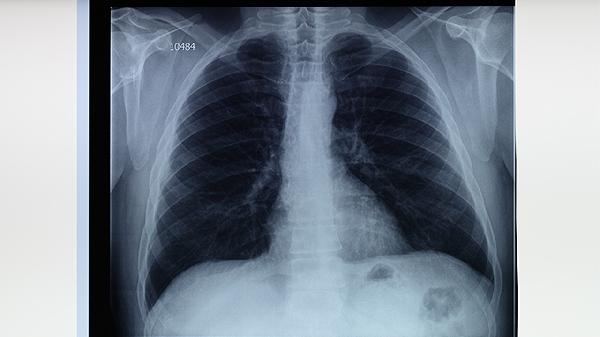

肺结核患者需坚持6-9个月的规范用药,即使症状消失也不可擅自停药。治疗期间应保持高蛋白饮食如鸡蛋、鱼肉,适当补充维生素丰富的新鲜蔬菜水果。注意隔离防护,咳嗽时掩住口鼻,痰液需消毒处理。定期复查胸部影像学和痰菌检查,出现药物不良反应及时就医调整方案。保持居室通风良好,避免劳累与情绪波动,保证充足睡眠有助于康复。